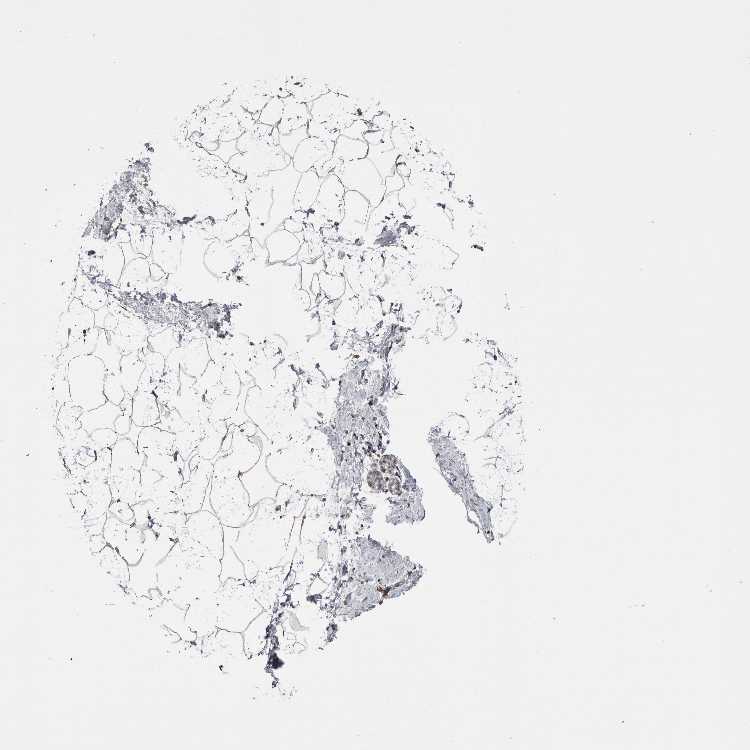

BREAST - Antibody stainingi

Antibody staining in the annotated cell types in the current human tissue is reported as not detected, low, medium, or high, based on conventional immunohistochemistry profiling in selected tissues. This score is based on the combination of the staining intensity and fraction of stained cells.

Each image is clickable and will lead to virtual microscopy that enables deeper exploration of all samples and also displays staining intensity scores, fraction scores and subcellular localization as well as patient and tissue information for each sample.

Antibody HPA018535Antibody HPA019569Antibody HPA019650Antibody CAB025135

Adipocytes LowNot detectedNot detectedNot detected

Glandular cells LowNot detectedNot detectedNot detected

Myoepithelial cells LowNot detectedNot detectedNot detected